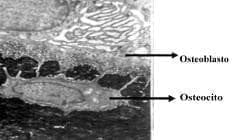

Figura 4. Macrofotografía electrónica. Se observa arriba un osteoblasto, con abundante retículo endoplásmico

característico y prolongaciones citoplasmáticas en contacto con un osteocito.

Son células derivadas de los osteoblastos, las más abundantes del hueso, encontrándose en proporción de 10:1 con los osteoblastos (Figura 4). Los osteocitos se comunican entre sí y con los osteoblastos por proyecciones citoplasáticas y al igual que los osteoblastos, se comunican con el endotelio, estableciendo un sincitio entre los osteocitos hasta la pared de los vasos sanguíneos (Figura 5).